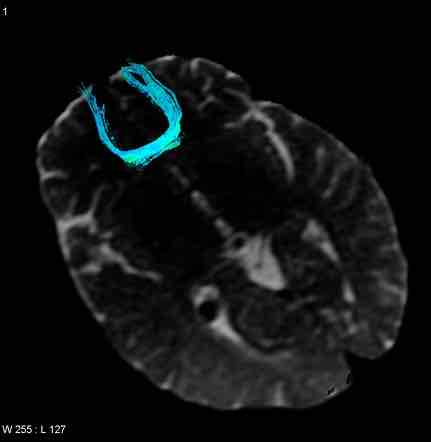

pęczek obręczy

w obrębie zakrętu obręczy, łączy płat czołowy i ciemieniowy z zakrętami przyhipokampowymi i potyliczno-skroniowymi